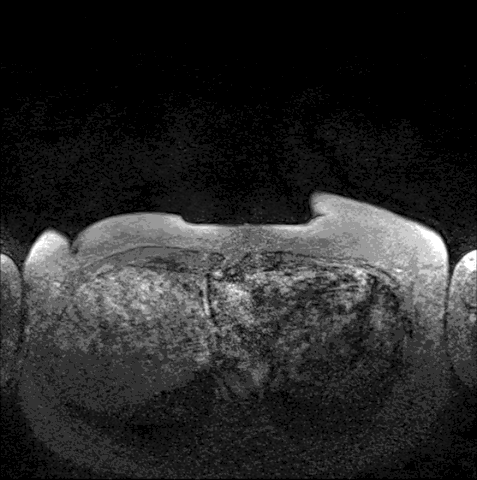

Október a mellrák-ellenes küzdelem hónapja. A WHO adatai szerint minden évben 458 ezer nővel végez a legelterjedtebb daganatos betegség, aminek megelőzése egy egyszerű otthoni vizsgálattal megoldható. Az, hogy mennyire elterjedt, mutatja, hogy számos híresség is megküzdött már a gyilkos kórral. Angelina Jolie még 2013-ban bejelentette, hogy kettős emlőeltávolításon esett át a rák magas kockázata miatt. Most megmutatjuk, kik azok, akik legyőzték a betegséget.